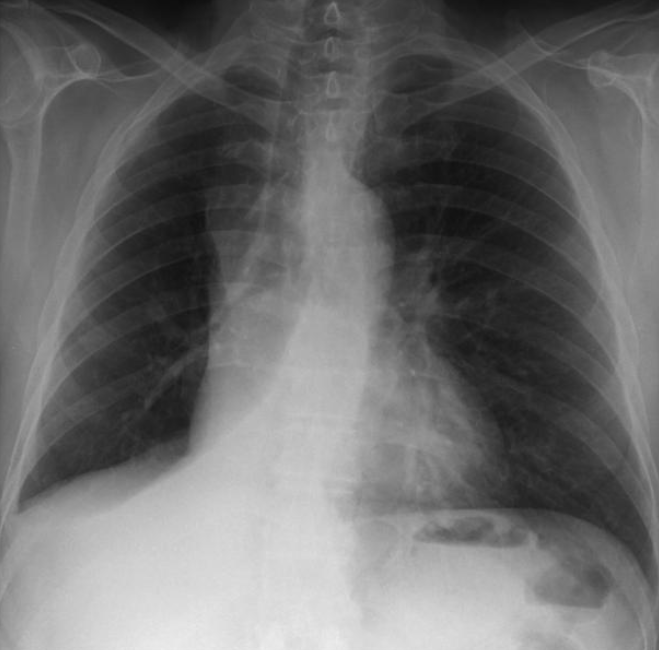

72세 여성이 복부 수술을 받은 다음날 경미한 호흡 곤란과 발열을 호소하였다. 혈압은 130/85 mmHg, 맥박은 88회/분, 호흡은 19회/분, 체온은 38.1°C로 측정되었다. 복부에는 수술 부위의 통증만 있었고, 압통이나 반발 압통은 관찰되지 않았다. 혈액 검사 결과와 가슴 X선 사진을 통해 진단을 내려야 한다. 가장 가능성이 높은 진단은 무엇인가?

WBC 11,300/mm3, Hb 12.9 g/dL, platelet 312,000/mm3

amylase 72 U/L(참고치, 22~130), lipase 20 U/L(참고치, 48~188)

pH 7.46, PaCO2 35 mmHg, PaO2 70 mmHg

Imp: 무기폐(atelectasis)

POD 1일에 발열, 호흡곤란을 호소하고 있으며 CXR상 RLL atelectasis가 관찰된다. 그 외 lung consolidation이나 pleural effusion은 명확하지 않으며, 수술부위 감염의 징후도 명확하지 않다.